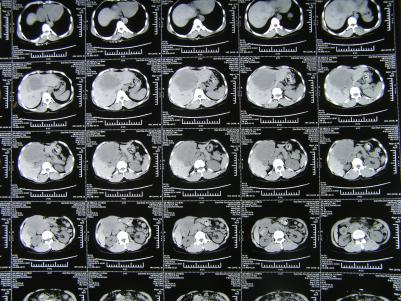

如解剖性精准肝叶、肝段切除,胰十二指肠切除,全胰腺切除,肝门部胆管癌根治(围肝门切除),胆管损伤修复,门脉高压断流、分流等。以下是部分手术图片。

一、肝切除

1. 肝门区域阻断超右半肝切除

2. 尾状叶切除

3. 肝s5/8段切除、胆管切除胆肠吻合

4. 肝s6段切除

5. 肝门区域阻断,s5段切

6. 肝s6、7段切除

7. 肝门部胆管癌根治,超左半肝切除+尾状叶切除,